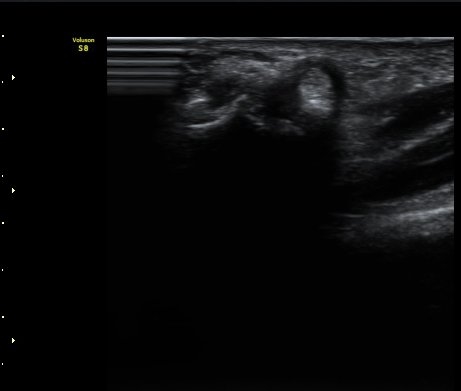

ºÎÁ¾ÀÌ °üÂûµÊ(±×¸² 1, 2). ÈûÁ٠Ⱦ´Ü¸é°Ë»ç¿¡¼­ A1ȰÂ÷ÀÇ Àú¿¡ÄÚ ºÎÁ¾ÀÌ °üÃÔµÊ(±×¸² 3).